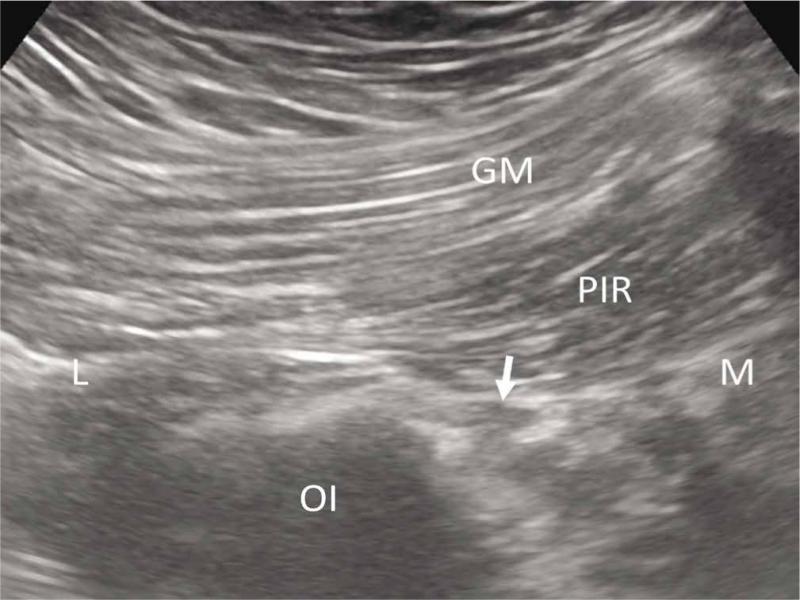

Fig. 2.